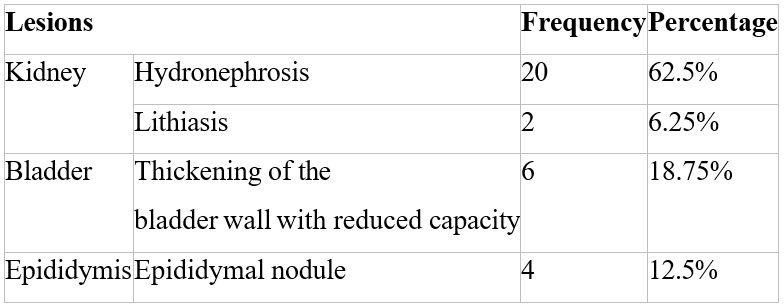

4.3 / Ultrasound: It was performed on all patients.

It revealed the following lesions (Table 3):

Table 3: Ultrasound abnormalities.